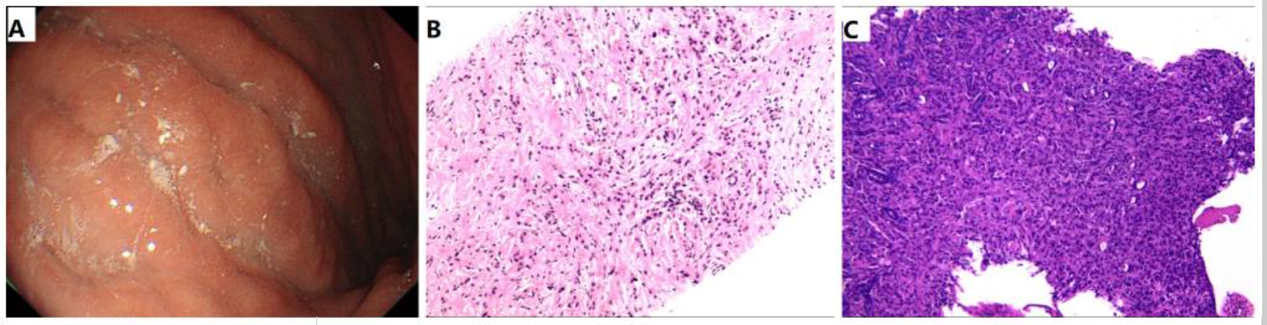

外周血肿瘤标志物检测显示多项指标显著升高:癌胚抗原(CEA)30.12 ng/ml(正常值≤5 ng/ml),糖类抗原125(CA125)321.1 U/ml(正常值<35 U/ml),细胞角蛋白19片段(CYFRA 21-1)117.5 ng/ml(正常值<3.3 ng/ml)。胃镜检查可见浅表萎缩性胃炎、胃底息肉,并在胃体部观察到浸润性病变(图2A)。

(A) 内镜视图显示胃黏膜充血、水肿,伴有浸润性病变,特征为黏膜皱襞僵硬和表面糜烂。(B) 乳腺活检组织HE染色显示出典型的浸润性小叶癌形态(放大倍数, ×10)。(C) 胃活检组织HE染色显示为腺癌(放大倍数, ×10)。HE,苏木精和伊红。

左乳肿块病理(图3):苏木精-伊红(HE)染色显示出典型的浸润性小叶癌形态学特征(图2B)。免疫组化(IHC)结果为:雌激素受体(ER)(-)、孕激素受体(PR)(-)、人表皮生长因子受体2(HER-2)(1+)、E-cadherin(-)、Ki-67(+,局部热点区达30%)、β-catenin(+)、细胞角蛋白(CK)5/6(-)、CK14(-)以及雄激素受体(AR)(++)。结合以上结果,明确诊断为经典型浸润性小叶癌,分子亚型为三阴性。

胃部病变病理(图4):HE染色提示为腺癌结构(图2C)。为鉴别其来源,进行了进一步的免疫组化检测,结果显示:ER(-)、HER-2(1+)、GATA结合蛋白3(GATA-3)(+)、CK7(++)、CK20(-)、Villin(-)。这一免疫表型组合(特别是GATA-3阳性及Villin阴性)有力地证实了胃部病变为乳腺来源的转移性腺癌。